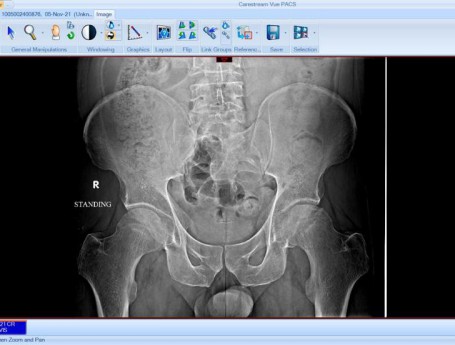

Total Hip Arthroplasty Anterior Approach

• Hip

خاصرة